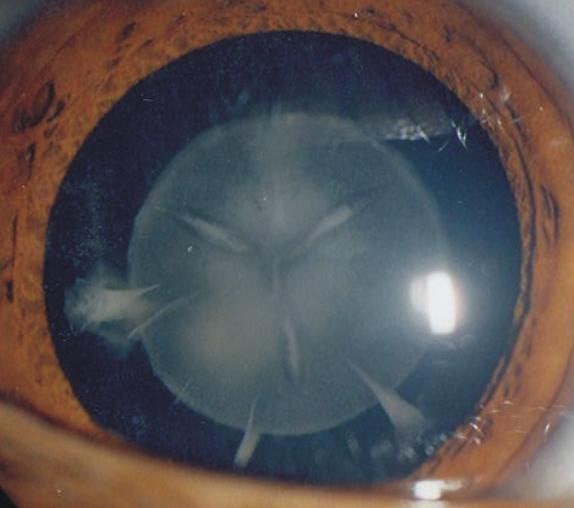

세 번째 사진이 봉합선 백내장 (sutural cataract)으로 흔한 형태이고 진행하지 않으며

시력에 영향이 거의 없습니다. 안과 외래에서 종종 관찰되며 걱정 안 하셔도 되는 백내장입니다.